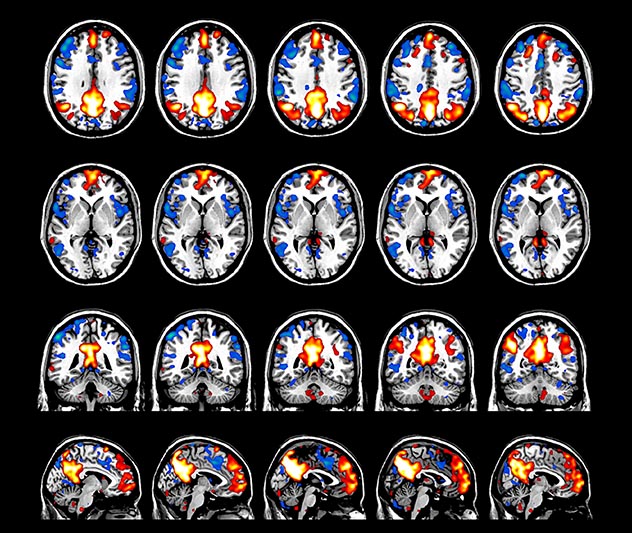

Resting state fMRI

Imaging was performed using Ingenia 3T CX with a 32ch dS Head coil, TR 1.6 sec, TE 35 ms, voxel size 3.1 x 3.1 x 3.1 mm, 46 slices and Multiband SENSE factor 2. Image provided by Dr. Gispert

Default mode network as discovered by resting state fMRI in one participant of the ALFA cohort [7]. rs-fMRI allows us to find networks of brain regions with highly correlated activity and sustaining distinct brain functions. The default mode network (in warm color scale) is active when the brain is focused on introspective thinking and has been shown to be altered in Alzheimer’s. Interestingly, brain areas of this network are known to show abnormal levels of one of the pathological hallmarks of Alzheimer’s (b-amyloid deposition) in preclinical stages. We want to better understand the alterations of these brain networks in preclinical stages of Alzheimer's and explore their potential use as biomarkers.

“We perform a resting-state fMRI sequence in all individuals of the cohort. Because of the vascular dynamics of restingstate in the brain, we feel it doesn’t make sense to go to shorter acquisition. So, we use MultiBand SENSE to double the amount of scans we acquire in a fixed amount of time. We are extremely happy with the quality we get for retrieving the default mode network. In about eight minutes, we acquire 300 volumes of 46 slices with an isotropic voxel size of 3 mm and a TR of 1.6 ms.”